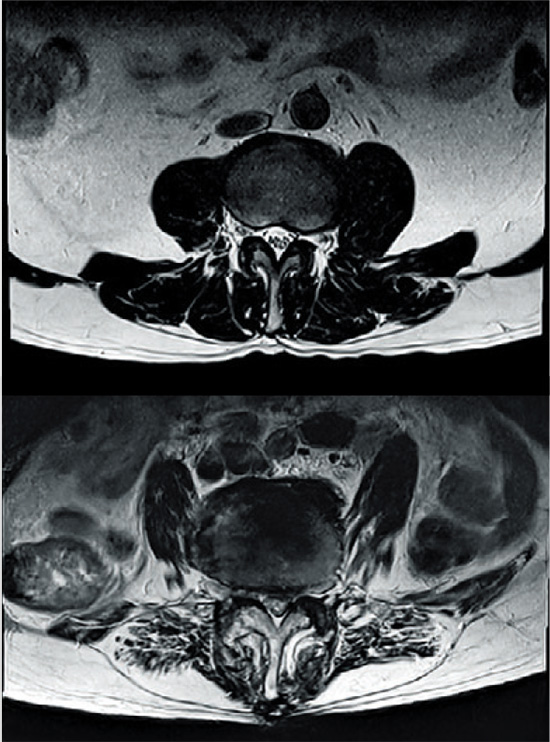

노년기에 허리가 굽는 또 다른 주요 원인은 척추관협착증이다. 척추관협착증은 척추 속 신경이 지나가는 통로인 척추관이 좁아지면서 신경근을 압박해 통증과 저림, 근력 저하 등을 유발하는 대표적인 퇴행성 척추질환이다. 건강보험심사평가원에 따르면, 국내 척추관협착증 환자는 2020년 165만9452명에서 2024년 185만6224명으로 11% 증가했다. 특히 60대 이상 장년층이 이 질환으로 병원을 많이 찾고 있는 것으로 나타났다.

척추관협착증 초기에는 허리가 묵직하거나 뻐근한 통증으로 시작하지만, 방치하면 엉덩이·허벅지·종아리까지 이어지는 '하지방사통'이나 조금만 걸어도 다리가 저려 쉬어야 하는 '간헐적 파행'으로 발전한다. 심한 경우 '내 살 같지 않다'고 표현하는 감각 이상이나 다리에 힘이 빠지는 근력 저하가 동반되기도 한다.

척추관협착증이 있으면 자신도 모르게 허리를 앞으로 숙이는 자세를 취하게 된다. 허리를 굽히면 좁아져 있던 척추관이 일시적으로 넓어져 신경 압박이 줄어들기 때문이다. 이는 척추관협착증이 '꼬부랑병'이라고 불리는 이유기도 하다.